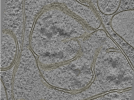

Photo Caption: Central slab from a representative tomogram of a Homo sapiens sample with selected set of annotations.

Cryo-electron tomography of FIB-milled HeLa PINK1-GFP cells treated with 10 uM Gamitrinib-triphenylphosphonium (G-TPP) for 4 hours to induce mitochondrial proteostatic stress. Data includes raw tilt series movie frames, assembled tilt series, tomographic reconstructions (WBP with and without CTF deconvolution), and automated segmentations of membranes. Acquired on a Titan Krios G4 with Falcon 4i detector and Selectris energy filter at 300 kV using dose-symmetric tilting with 3 degree increments. Cryo-FIB milling was performed on an Aquilos 2 cryo-FIB/SEM to produce lamellae of less than 250 nm thickness.